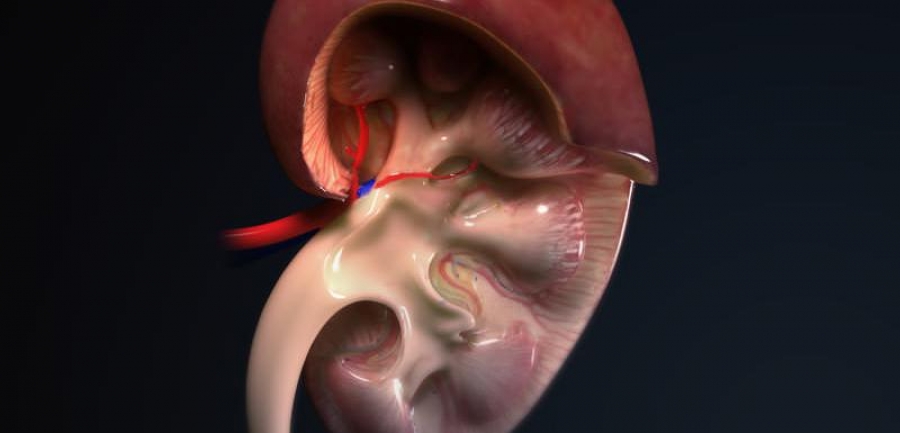

Krv u urinu

Krv može da bude simptom uvećane prostate ili kamena u bubregu ili čak raka.

Ovo upućuje da imate previše proteina u mokraći, što znači da vaši bubrezi ne rade svoj posao kako treba. Ovaj simptom može da bude znak početka razvoja dijabetesa ili bolesti bubrega.